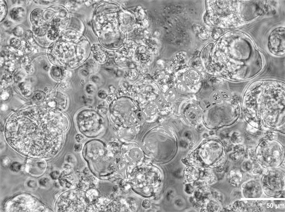

研究团队通过差速超速离心法从健康牛乳中分离 sEV,经鉴定后采用共孵育法(ICA 与 sEV 按 1:9 比例,22℃孵育 24h)制备 sEV-ICA,关键特性如下:

sEV 鉴定符合标准:Western blot 显示 sEV 表达 CD63、CD81、ALIX 等标志性蛋白,不表达微囊泡标志物 CD40。TEM 观察到典型脂质双层结构,粒径 30-150nm。NTA 检测平均粒径 116.8nm,浓度 6.9×10⁶ particles/mL。

sEV-ICA 特性稳定:负载 ICA 后,sEV 仍保持脂质双层结构,平均粒径仅轻微增加至 124.3nm。HPLC 检测药物负载率为 5%-8%,且在 GelMA 水凝胶中可实现长期缓释。

sev和sev-ICA的准备和识别 (Xinxin et al ., 2023)